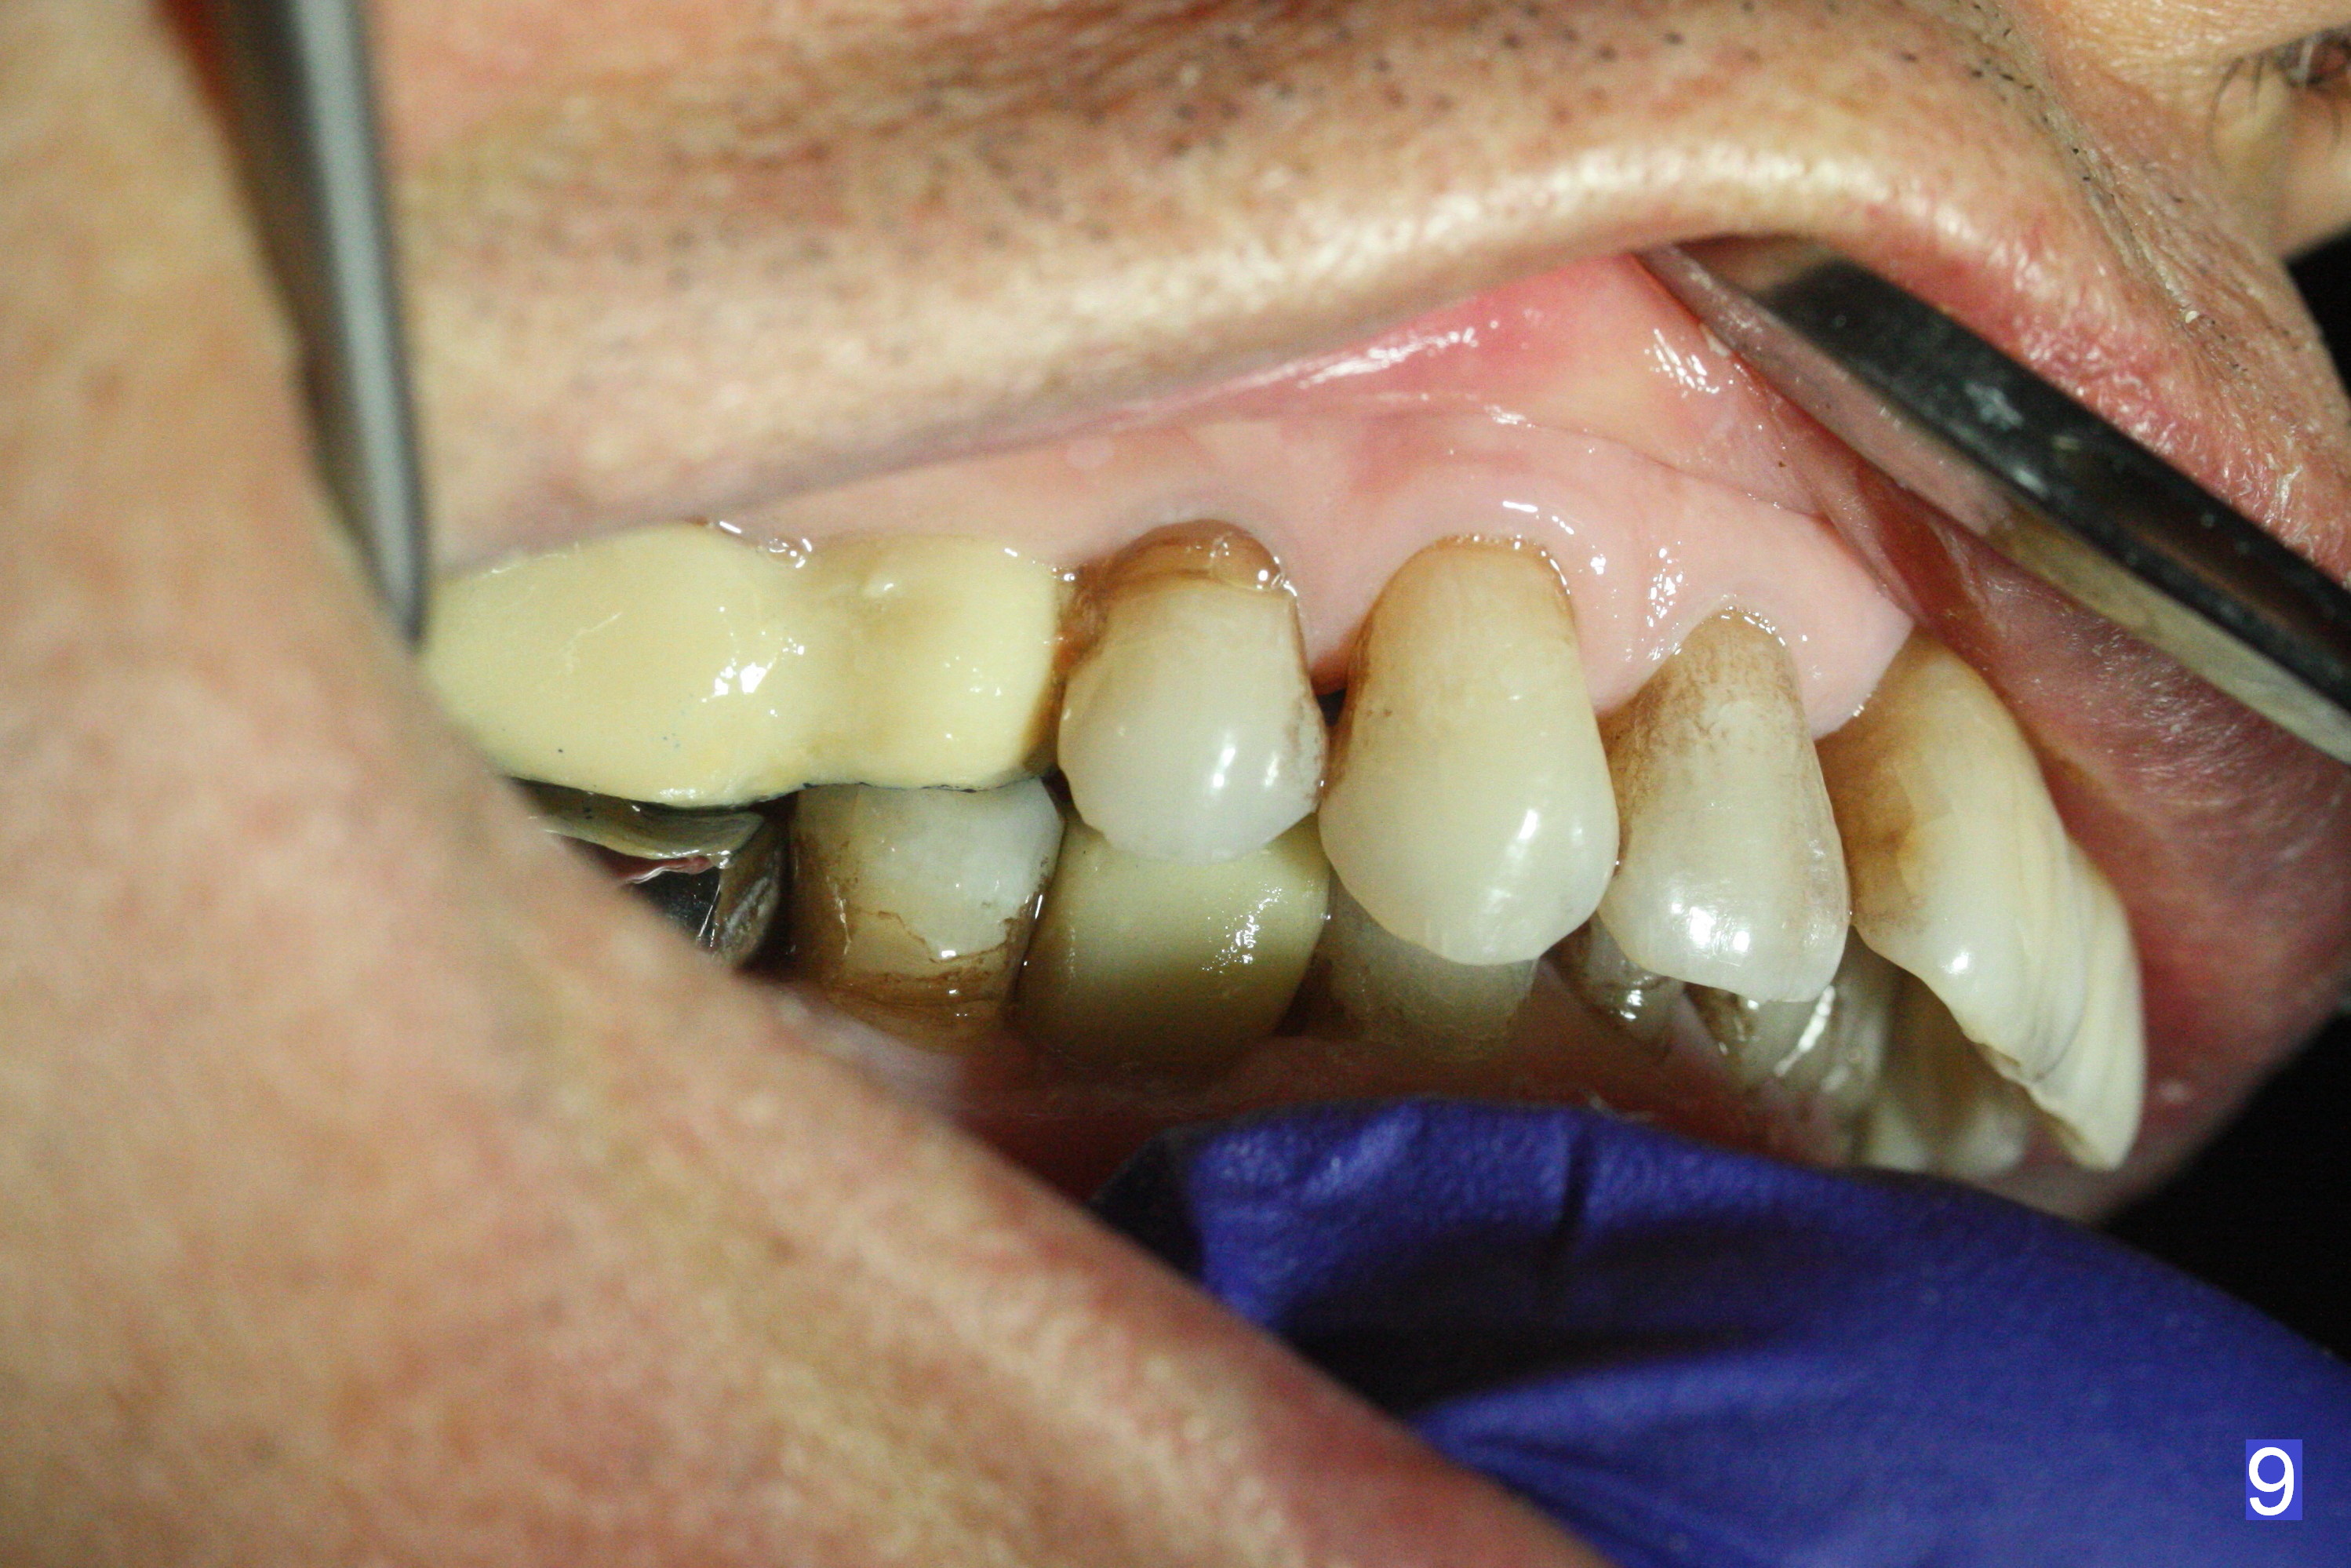

The fistula buccal to #14 remains 1 week postop (Fig.7) and disappears 1 months postop. The fistula does not re-appears 3 months postop with the implants at #13,15 apparently osteointegrated (Fig.8). With relining #13-15 provisional with increased vertical height (Fig.11), the patient has bilateral posterior contact (Fig.9), while the lower incisors do not contact the cinguli of the upper incisors (Fig.10 *). The space between the tooth #12 and the pontic #21 is unfavorable for posterior occlusal stability (Fig.11 *). Porcelain is chipped off the buccal surface of the pontic (Fig.12 *). If the patient does not afford an implant at #21 with redo crowns at #20 and 22 (Fig.13), what else could be done? He will return for #15 implant placement 4 months post socket preservation.